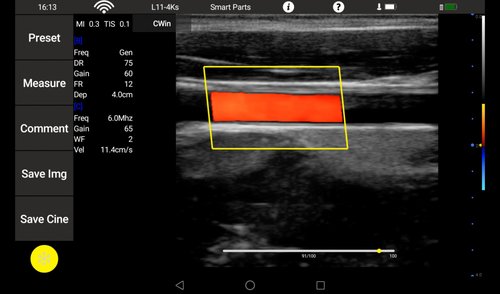

Linearsonde (L11-4Ks) 7,5 MHz 6-11 MHz L40 Gefäße, Small Parts, Anästhesie, Orthopädie

• Color: B, M, 2B, 4B, THI, Color, Power, PW